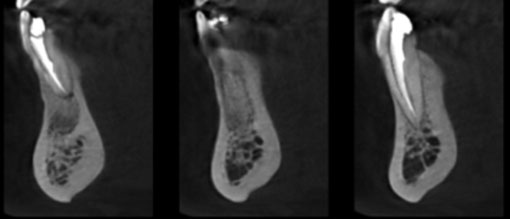

L’examen radiographique montre effectivement une radioclarté apicale au secteur incisivo canin mandibulaire, à contours nets, sans résorption radiculaire associée. Le cone beam réalisé précise le volume exact de la lésion, ses rapports aux apex voisins, et met en évidence la rupture de la continuité de la table externe, liée au volume lésionnel. La table linguale est par endroit érodée, mais continue (2).

Un cone beam est également réalisé, et montre une parfaite consolidation osseuse, et la conservation d’un relief naturel au niveau mentonnier. Les régions apicales de chacune des dents est de radio densité osseuse.